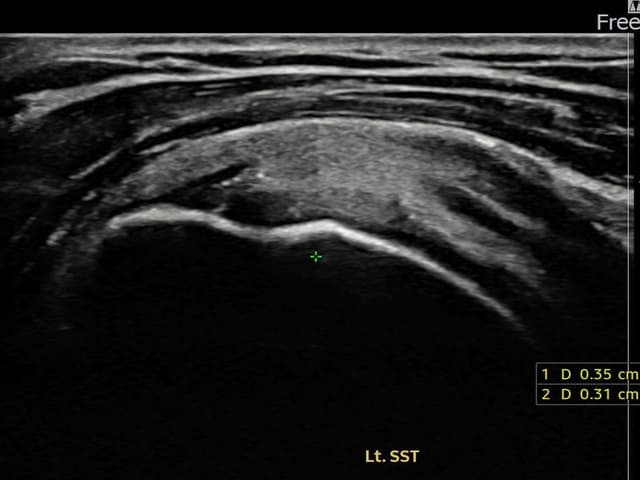

[経過期間: 24.01.08~24.03.14]

[縫縮術] 超音波検査にて左 棘上筋腱 関節面側部分断裂(3.5mm × 3.1mm (부분파열))を確認。縫縮術施行後、腱の連続性が回復し、日常生活に復帰されました。